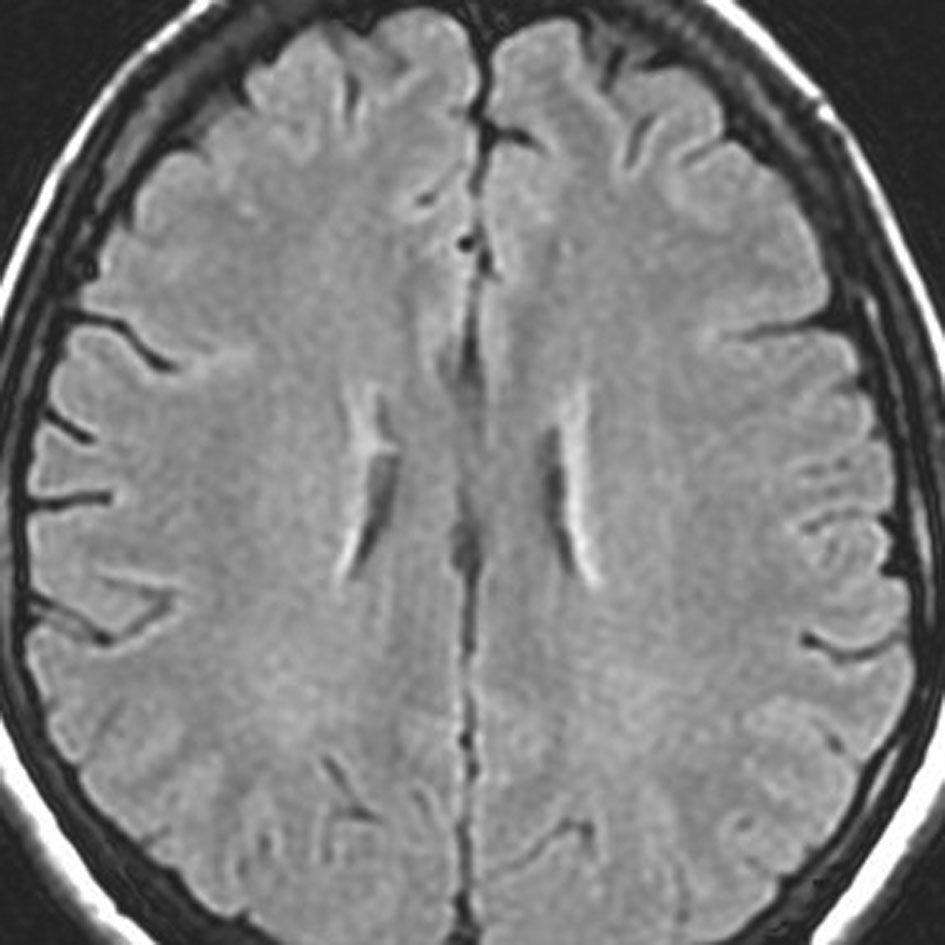

左前頭葉のグリオーマ oligodendroglioma に54グレイ27分割の放射線治療が行われました。治療直後のフレア画像(左)では深部白質に異常信号はありません。

2年後のフレア画像です

側脳室壁と深部白質 (半卵円中心) にびまん性の高信号が出現しています

無症状です

グリオーマが再発したのではないかと思ってしまいますが違います

5年後のフレア画像です

ごくわずかに広がりましたが,このくらいでで止まります